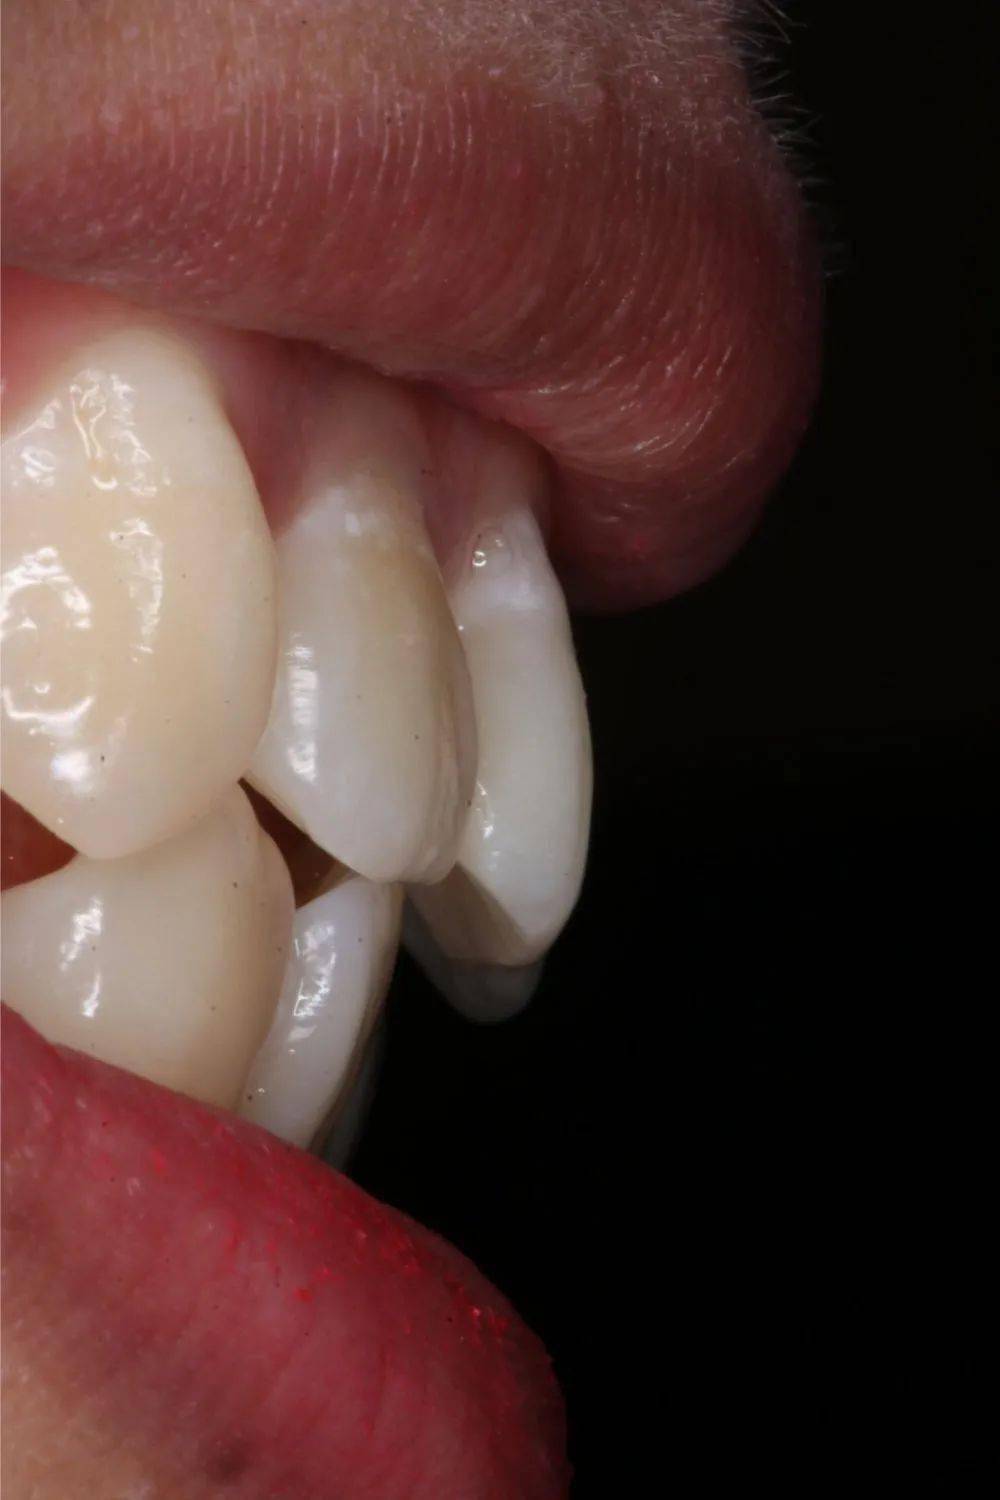

经过几个月后 , 渐渐可以看到

嘴凸问题得到了缓解 , 下巴更明显

尤其脸型曲线变得很柔和

侧面线条流畅

3个月后

文章图片

6个月后

9个月后

矫正10个月后 , 牙齿已经变整齐了很多